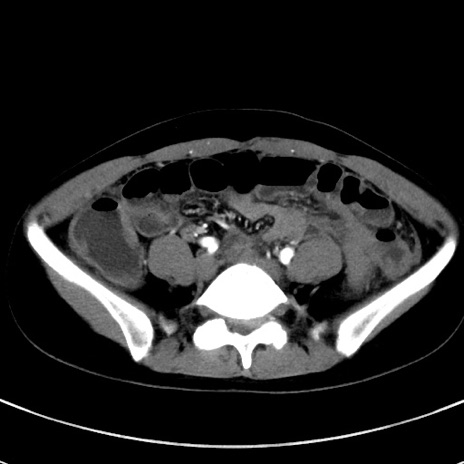

症例17(横断像)

【症例】20歳代女性

【主訴】嘔吐、下腹部痛

【現病歴】昨日夕食後に嘔吐し下腹部痛が出現。本日になっても嘔吐持続し改善しないため来院。

【身体所見】意識清明、BT 37.2℃、BP 108/67mmHg、腹部:平坦、やや硬、下腹部正中から右にかけて圧痛あり、反跳痛軽度あり、tapping pain(+)。

【データ】WBC 13600、CRP 14.94